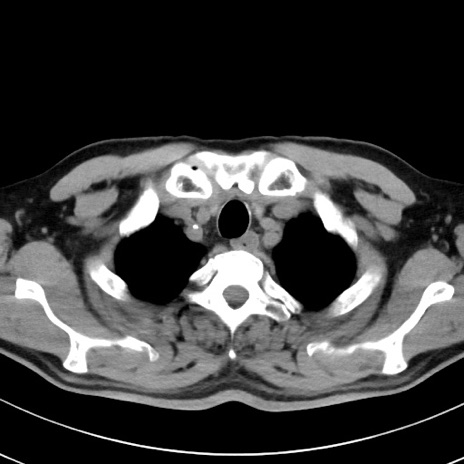

【腹部TIPS】症例29 参考症例 CT(横断像)

症例

70歳代男性